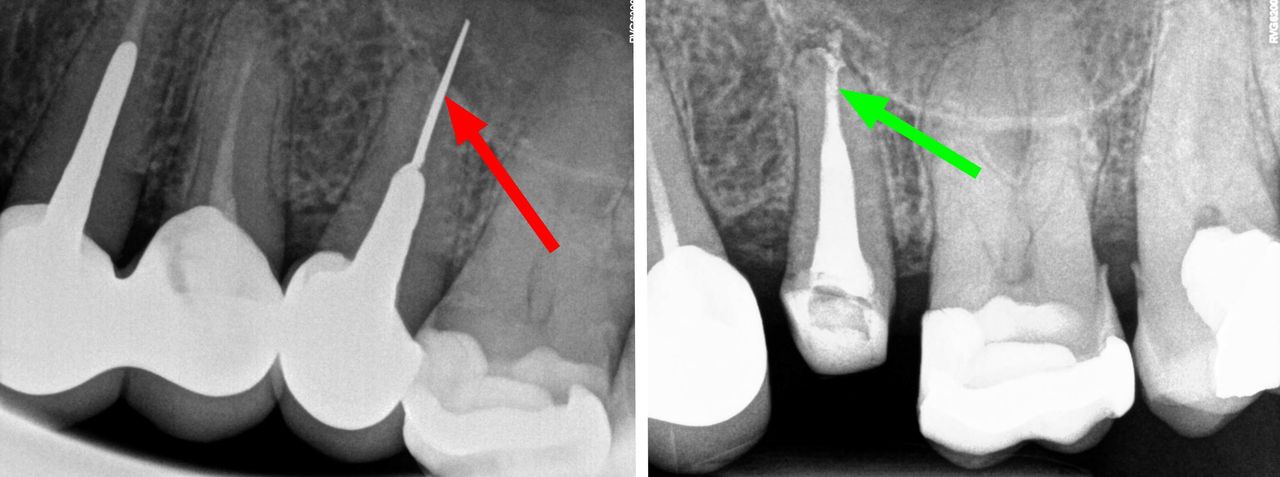

- Usuwanie złamanych narzędzi kanałowych oraz innych ciał obcych pozostawionych w kanałach korzeniowych

- Zamykanie perforacji w korzeniach zębów

- Specjalizujemy się w powtórnym leczeniu kanałowym i leczeniu powikłań co oznacza, że mamy wieloletnie doświadczenie w usuwaniu złamanych instrumentów kanałowych w szybki, bezbolesny i nieinwazyjny sposób. Dr Gończowski jest autorem specjalistycznego zestawu mikroinstrumentów (FRS®) przeznaczonych do usuwania ciał obcych z kanałów korzeniowych